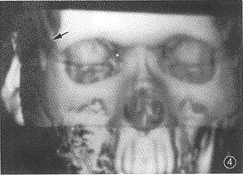

(4)X線拍片對本病的早期診斷價值不大,晚期可顯示上頜骨骨質疏鬆、破壞及死骨形成等。